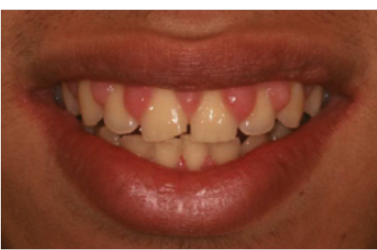

电刀怎么洗我以为只要洗个牙,医生你怎么还拿起了手术刀?_https://www.jmylbn.com_新闻资讯_第5张

治疗后

电刀和激光都有止血功能,因此这种手术出血量较小,愈合时间也不会过长,大家也不必过度抗拒。